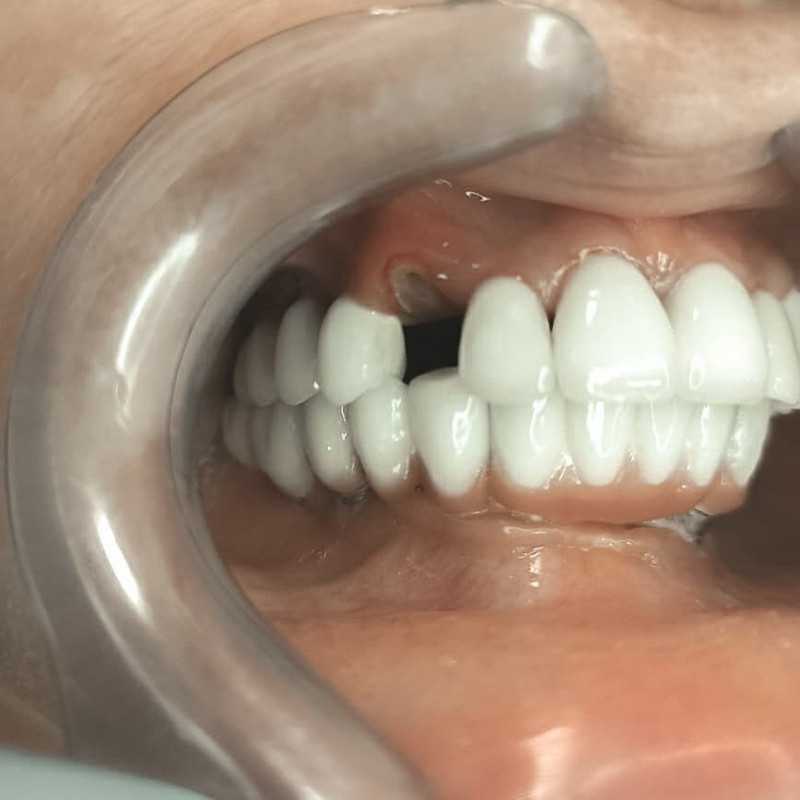

Имплантация верхнего зубного ряда по протоколу немедленной нагрузки

Доктор: Дровосеков Михаил Николаевич